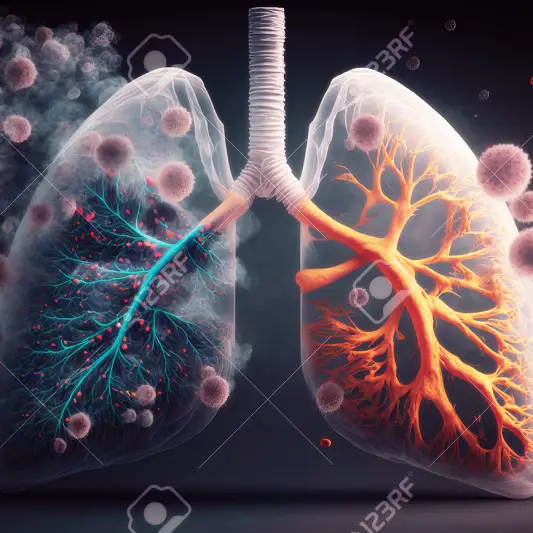

후송 기간 동안의 정신적 지원

폐암 수술 후의 관리와 후송 기간은 매우 중요합니다. 수술로 인해 신체적으로 힘들어지는 동시에 정신적인 지원도 필요하기 때문입니다.

폐암 수술 후, 신체의 회복에는 많은 시간과 노력이 필요합니다. 수술 부위의 통증과 피로감 때문에 일상 생활에 적응하는 것이 어렵고, 이로 인해 정신적인 스트레스가 발생할 수 있습니다.

이러한 상황에서는 후송 기간 동안 정신적인 지원이 매우 중요합니다. 가족이나 친구와의 이야기, 상담사의 도움, 혹은 정신적인 힘을 주는 취미나 활동에 참여하는 것이 도움이 될 수 있습니다.

정신적인 지원을 받는 것은 신체적인 회복을 돕는 데에도 큰 도움이 됩니다. 스트레스와 불안을 감소시키고 긍정적인 마인드를 유지하는 것은 신체의 회복 속도를 가속화시킬 수 있습니다.

후송 기간 동안의 정신적인 지원은 폐암 수술 후의 복잡한 상황에서 많은 도움을 줄 수 있습니다. 가족, 친구, 전문가의 도움을 받으면서 체력과 정신력을 회복해 나갈 수 있도록 노력해야 합니다.

폐암 수술후 필요한 관리와 후송 기간에서 정신적인 지원은 단지 힘이 되는 것이 아니라, 완전한 회복을 위한 필수적인 조건이라고 할 수 있습니다. 이를 잘 이해하고 적절한 지원을 제공함으로써 폐암으로 인한 어려움을 극복하는 데 도움이 되길 바랍니다.